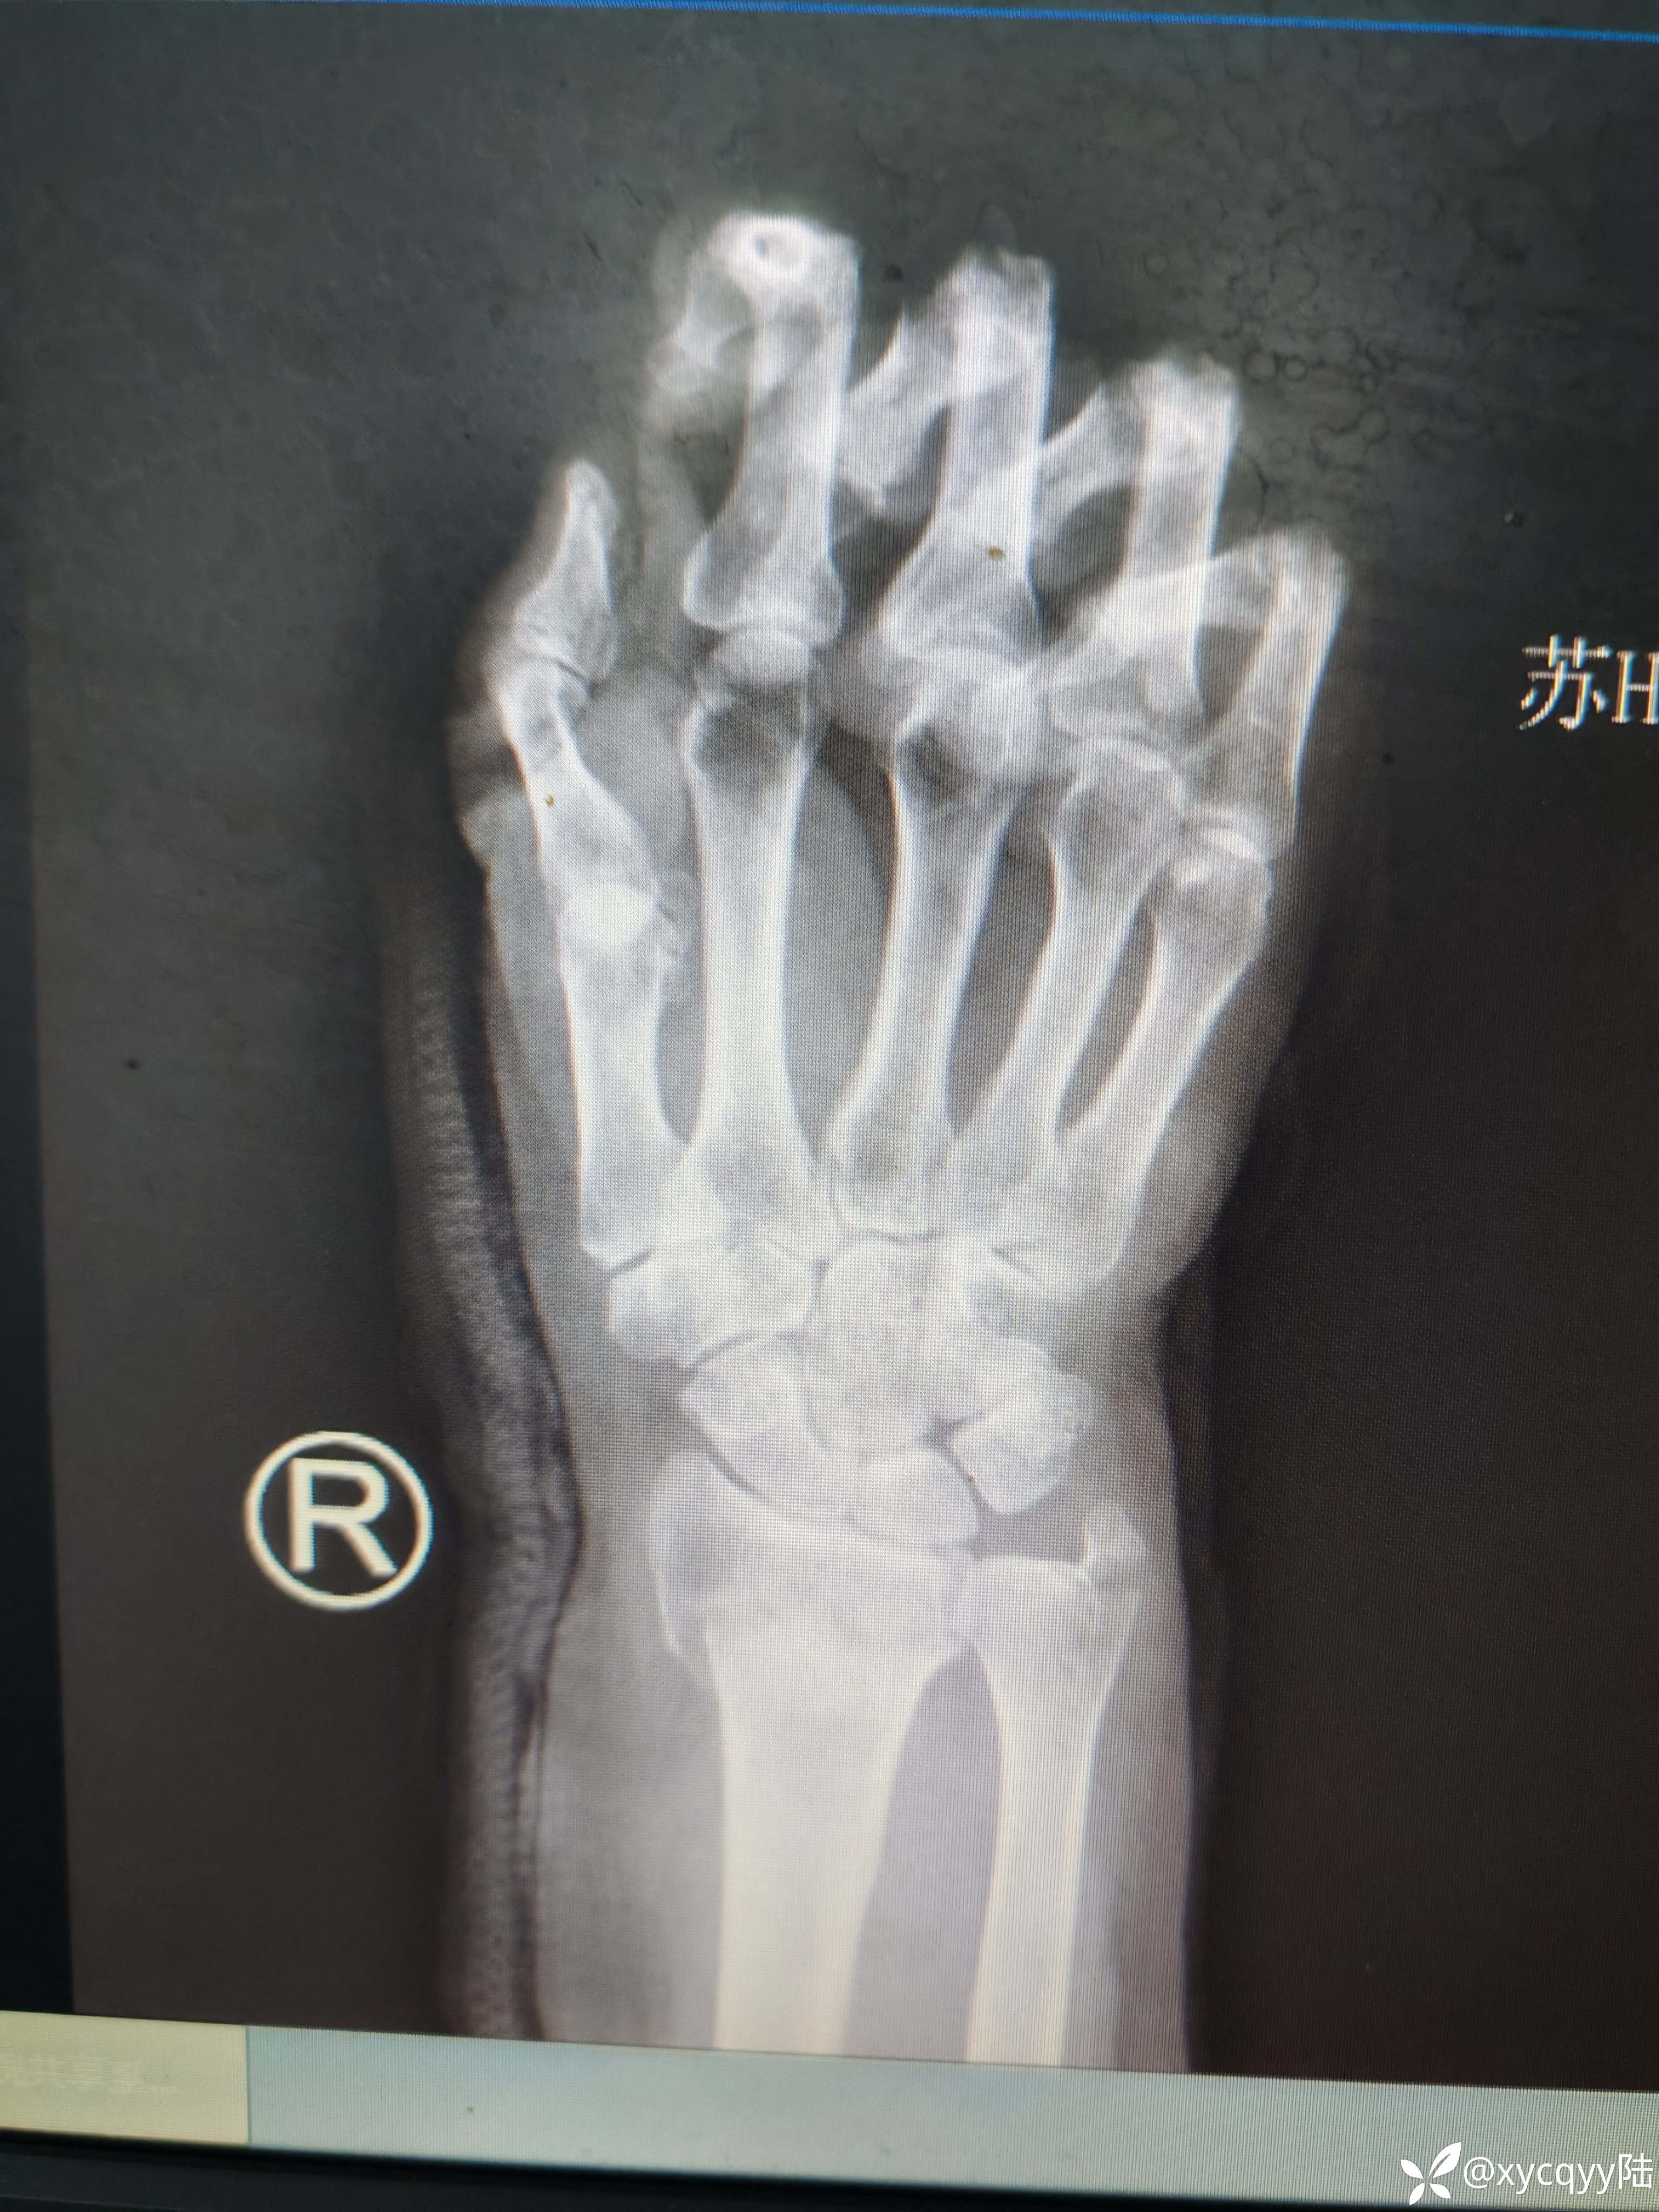

女,60岁,外伤桡骨远端骨折尺骨茎突骨折复位后效果